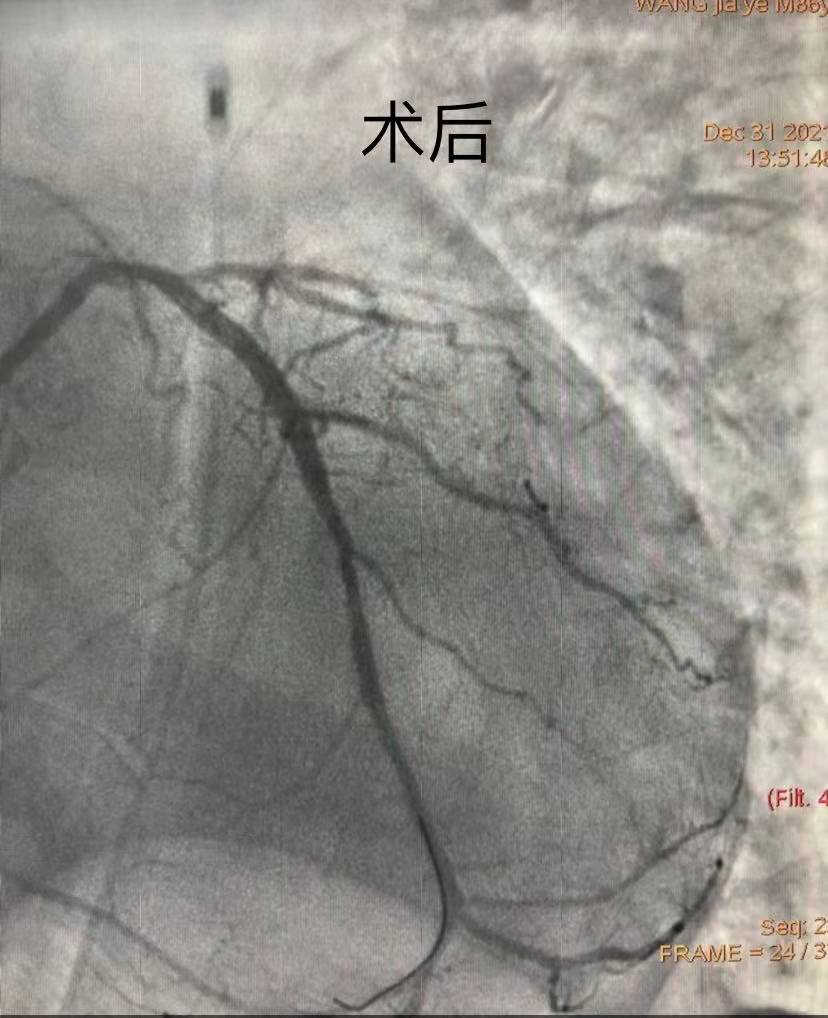

團(tuán)隊(duì)綜合考慮后判斷,LCX是此次心肌梗死的“元兇”。開(kāi)通病變部位的機(jī)會(huì)只有一次,必須做到“快、準(zhǔn)、狠”。汪院長(zhǎng)團(tuán)隊(duì)經(jīng)驗(yàn)豐富,技術(shù)嫻熟,導(dǎo)絲小心通過(guò),球囊充分?jǐn)U張,最后在病變部位植入支架,所有操作一氣呵成。復(fù)查造影顯示,病變部位狹窄小于10%,手術(shù)獲得成功。

術(shù)后72小時(shí)尤為重要,心血管內(nèi)科團(tuán)隊(duì)不敢有絲毫懈怠,護(hù)士長(zhǎng)彭鳳艷帶領(lǐng)護(hù)理團(tuán)隊(duì)嚴(yán)格床旁交班,事無(wú)巨細(xì)地交代注意事項(xiàng)、皮膚及管道護(hù)理,嚴(yán)密監(jiān)測(cè)患者生命體征。三天后,患者生命體征逐漸平穩(wěn)。1月3日經(jīng)綜合評(píng)估后,拔除IABP導(dǎo)管,復(fù)查心臟彩超,各項(xiàng)評(píng)分?jǐn)?shù)值恢復(fù)良好。經(jīng)過(guò)10余天的精心治療和護(hù)理,患者于1月12日康復(fù)出院。